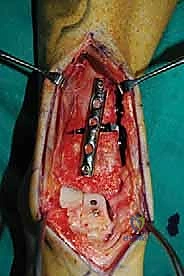

الغوص العميق في جراحة الطعم الخيفي الهيكلي (Structural Allograft Reconstruction)

يهدف هذا الإجراء العبقري إلى استبدال الغضروف والعظم التالفين والميتين بنسيج سليم تماماً مأخوذ من متبرع متوفى (طعم خيفي - Allograft). هذا الطعم يتم تعقيمه وحفظه في بنوك الأنسجة العالمية وفقاً لأعلى المعايير الطبية الصارمة لضمان خلوه من أي أمراض معدية والحفاظ على حيوية الخلايا الغضروفية.

- الترميم التشريحي الحقيقي: يسمح باستعادة الشكل الهندسي الدقيق لعظم الكاحل، بما في ذلك المنحنيات المعقدة لكتف التالوس.